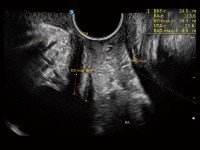

夢(mèng)溪?P80以“關(guān)愛(ài)女性”為基石,提供全方位的解決方案,量身定制以滿(mǎn)足女性的健康需求,涵蓋婦科、生殖健康檢查、產(chǎn)前篩查及產(chǎn)后康復(fù)等領(lǐng)域。

通過(guò)工作流協(xié)議、遠(yuǎn)程訪(fǎng)問(wèn)、自動(dòng)探頭激活和人體工程學(xué)優(yōu)化設(shè)計(jì)等功能,旨在提高臨床工作效率